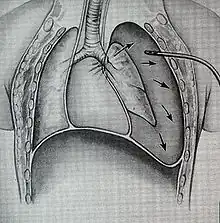

a)Collapsed right lung , left deviated trachea , and shifted heart b) chest illustrating collapsed right lung and shifted heart -